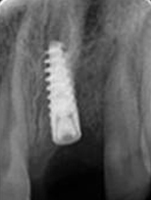

X-ray of Implant

Single Tooth Implant

Placement of Bone Grafting